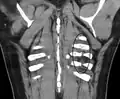

Fracture de côte sur un scanner thoracique Fracture de côte sur un scanner thoracique